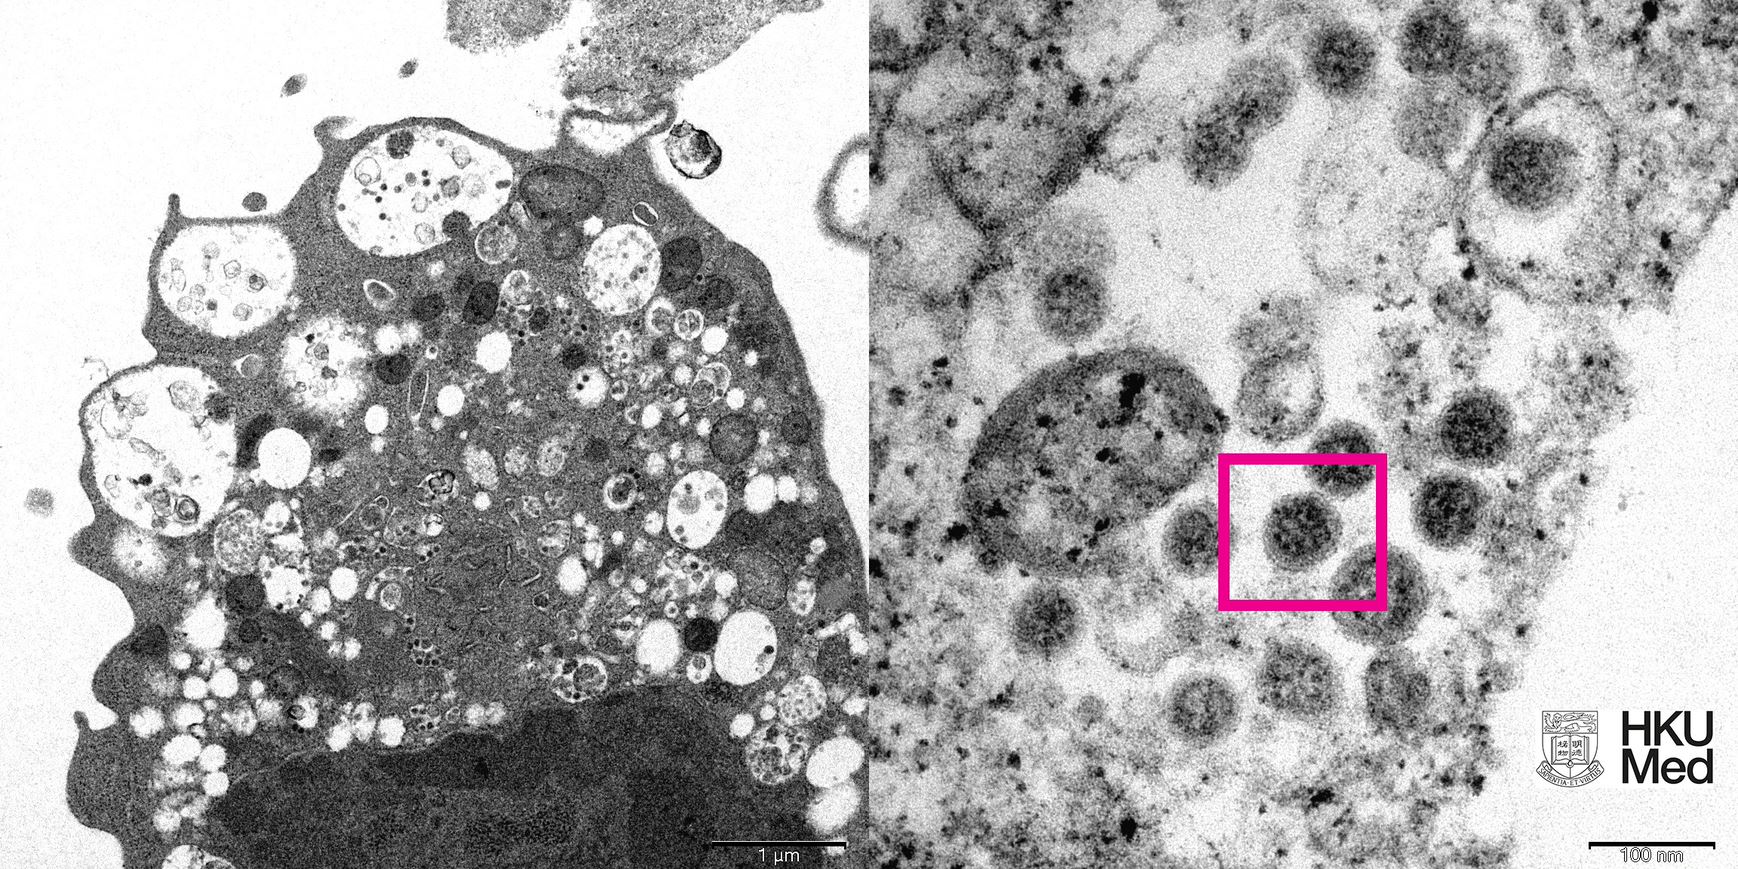

研究人員在低倍電子顯微鏡下,觀察感染新型冠狀病毒Omicron變異株後的猴腎細胞(Vero E6)。照片顯示細胞受損,腫脹囊泡,囊泡內含有黑色小病毒顆粒;在高倍電子顯微鏡下,觀察受感染的Vero E6細胞,照片顯示病毒顆粒表面呈現皇冠形的刺突蛋白。